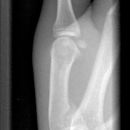

Bennett Fraktur

Bennett Fraktur mit geringer Dislokation